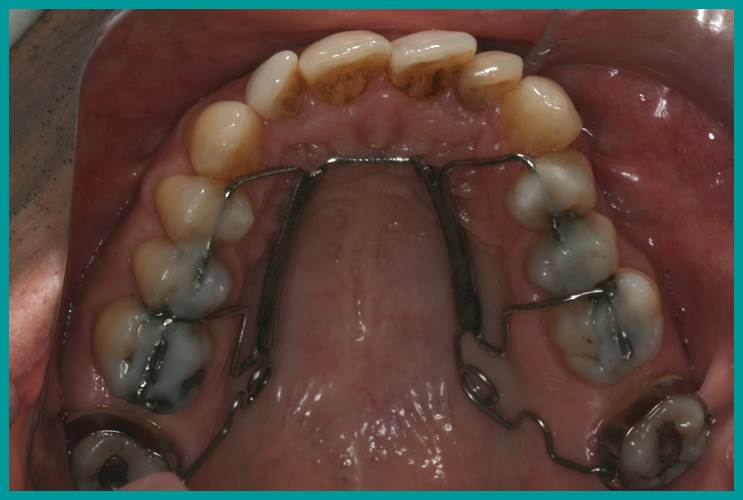

Casos BBO

Caso 3

PACIENTE:

Sexo Masculino | 32 anos | Leucoderma

Observações do Caso:

Anteroposterior:

Classe II, divisão 1 subdivisão direita

Transversal:

Suave atresia na maxila

Vertical:

Trespasse vertical deficiente

Incisivos superiores:

Girados e verticalizados na base

Incisivos inferiores:

Alinhados e bem posicionados

Queixa Principal:

Apinhamento anterosuperior